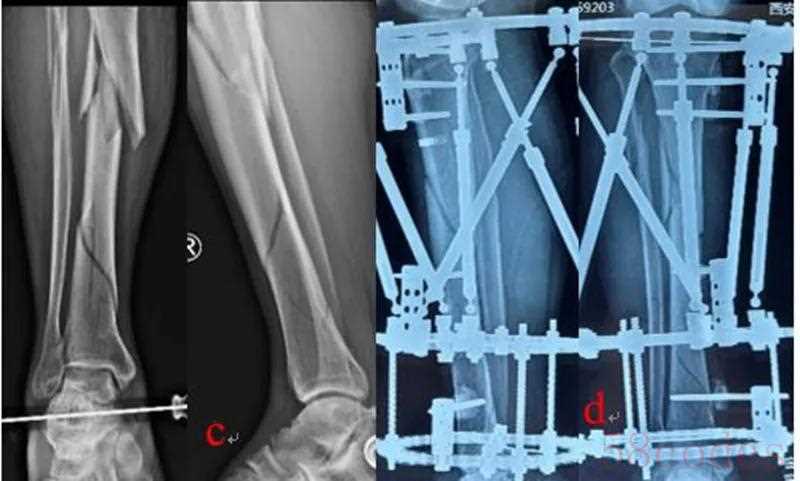

王学等利用国内自主研发的数字六轴外架(QSF)治疗膝关节复杂畸形,钟豪良等利用QSF治疗成人Blount 病,均取得良好疗效。该数字六轴外架配套软件基于CT数据,亦是目前国际上唯一的基于CT数据的配套软件,所以复位精度更高,而且其复位精度不受外固定架的安装位置、X线放大率、拍摄角度等的影响。所以与国际上的其它六轴外架产品比较,具有复位精度高,操作简便、学习曲线短等优点。临床使用时,医生不需要测量骨折或畸形的6个移位参数,以及环的4个安装参数,后台工程师根据CT数据计算6根连接杆的调节数据,医生根据该数据,将各连接杆的长度调节到位即可。优点是复位精度高,对外固定架的安装无特殊要求,操作更简便,降低医生的学习曲线,同时大大简化了临床医生的繁琐工作,也不需要医生学习掌握软件操作。但由于不是医生自己测量和软件运算,所以不能实时获得处方。

图3:QSF结合内固定治疗双侧Blount病 a:术前双下肢力线;b:畸形分析:股骨外翻,胫骨内翻、内旋、短缩;c、右侧股骨远端闭合截骨即时矫正内固定、六轴外架缓慢矫正胫骨畸形;d:左侧股骨远端内侧闭合截骨即时矫正内固定、六轴外架缓慢矫正胫骨畸形;e:双侧矫形术后,力线恢复良好,内旋纠正,双下肢等长。